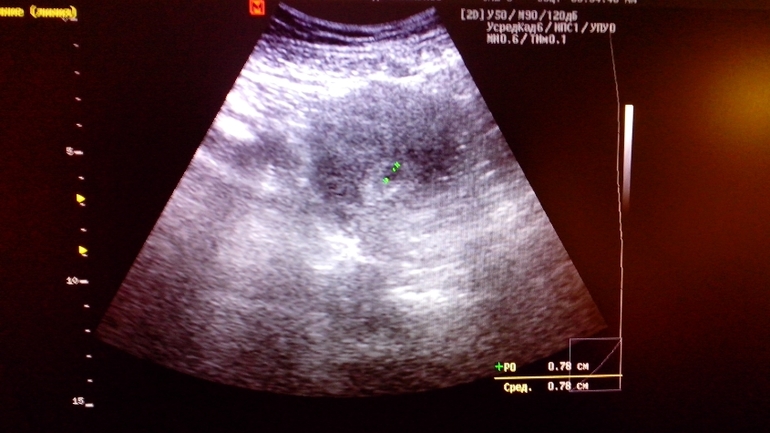

ДругоеДевочки мои миленькие,ББ-шечки!!!После 11 лет безуспешных попыток снова стать мамой,все получилось!!!!!И этот страшный диагноз-вторичное бесплодие канул в лету!!!!!Много изменений произошло с момента моего последнего посещения сайта,но как говорят:все что не делается-все к лучшему))))Я здесь уже 2 года,последнее время бывала конечно очень редко,но сейчас я просто обязана поделится радостной новостью с вами,ведь меня поддерживали мои новые подружки,которых я нашла здесь,на этом позитивном сайте!!!Я сама не верила ни одному тесту,которых за 2 дня задержки сделала аж 6 штук,пока не побежала на УЗИ и там врач мне сказала:Беременность есть,3 недельки!!!)))))Так как по возрасту я нахожусь уже в зоне риска,я все же хочу,чтоб у меня все разрешилось благополучно,ведь главное не отчаиваться и верить,что все получиться!!!!!!11 лет бесплодия и вера в исполнение желаний подтверждают это!!!!!